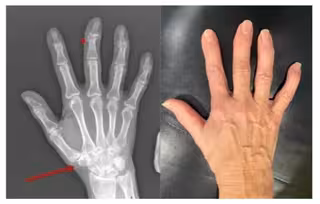

Остеоартроз розвивається поступово, і перші симптоми можуть бути майже непомітними – легка ранкова скутість, дискомфорт після фізичного навантаження або короткочасний біль у суглобах. З часом хрящова тканина втрачає еластичність, з’являється тертя, запалення й характерний «хрускіт», що заважає рухатися вільно. До ключових причин належать вікові зміни, надмірна вага, травми, спадкові фактори чи надмірні навантаження. Якщо процес прогресує, погіршується якість життя, зменшується обсяг рухів і зростає ризик деформацій.